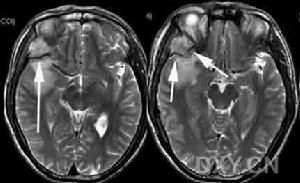

乾骺端或骨幹蟲蝕狀、斑片狀、泡沫狀或大片狀溶骨性破壞,邊緣不清破壞區內有大小不一的殘留骨嵴。破壞嚴重者出現病理性骨折腫瘤侵及骨皮質使其變薄和輕度擴張。亦可穿破骨皮質侵入軟組織,形成軟組織腫塊。少數病例可見少量成骨現象,有骨膜反應或Codmon三角。